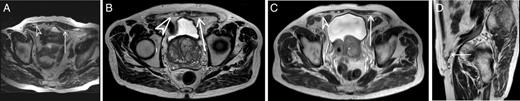

During the follow-up period of 3 years, the patient had three abdominal MRIs (Fig. 2A–D). Both meshes are visible 1 month postoperatively as a dark linear structure (Fig. 2A). When comparing the absorbable mesh 1 month after operation with 2 years after operation (Fig. 2B), the thickness of the dark line had been slightly reduced. The thickness seemed to be unaltered between the second and the third postoperative years (Fig. 2C). The signal voids in Fig. 2B and C have the same intensity, and it is impossible to assess if the dark line seen in the left groin after 2 and 3 years represents the absorbable mesh or new connective tissue. In contrast to this, the thickness of the permanent mesh was stable during the 3 years. The permanent mesh and the absorbable mesh/new connective tissue are also visible in a sagittal image 3 years postoperatively (Fig. 2D).

MRIs of the patients’ groins during the follow-up. Arrow indicates the absorbable mesh/new connective tissue. Arrowhead indicates the permanent mesh. Asterisk indicates the permanent mesh. (A) Axial T2-weighted image, 1 month postoperative. (B) Axial T2-weighted image, 2 years postoperative. (C) Axial T2-weighted image, 3 years postoperative. (D) Sagittal T2-weighted image, 3 years postoperative.